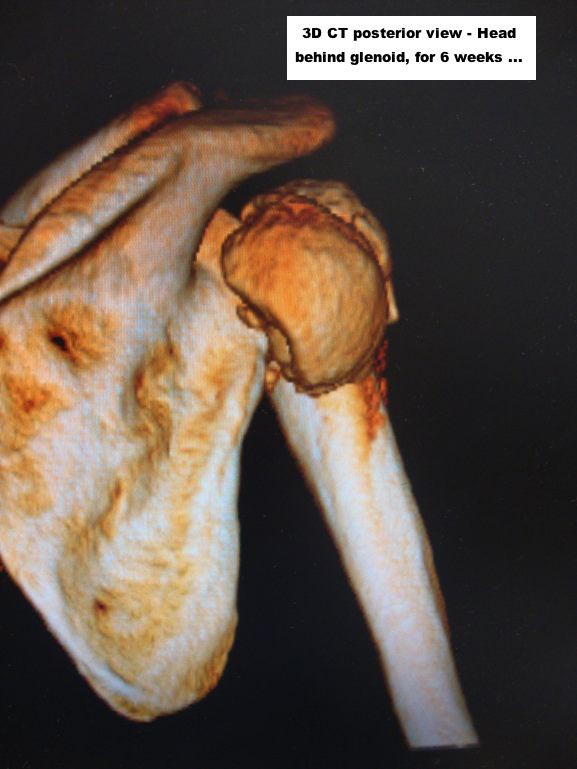

Here are some photos, of chronic, locked, 4 part posterior dislocation, 2 months old, that I did September/2011. Patient is 67, very, very active - had a really reasonable, honest clinical result ...

Photos attached ...